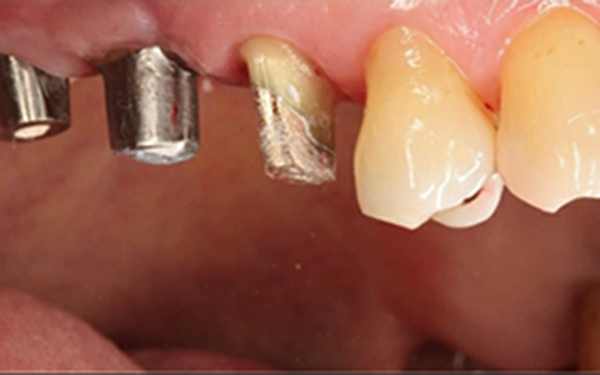

植牙合併無敲擊水壓式上頷竇增高術

X光片顯示骨頭成功增高